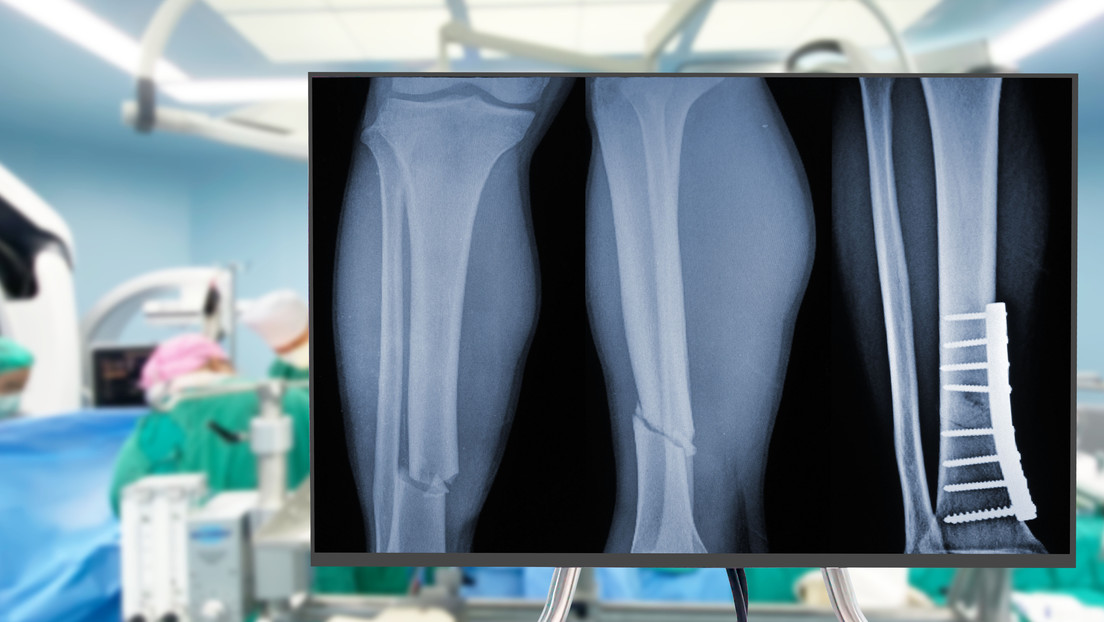

Gracias a su tecnología adhesiva, el pegamento, bautizado como Bone 02, ha logrado unir y fijar en unos pocos minutos distintos fragmentos óseos mediante una incisión de 2 a 3 centímetros que resulta mínimamente invasiva.

El material, inspirado en las ostras, representa un avance significativo respecto de los procedimientos tradicionales, que utilizan placas de metal para recuperar los huesos atendidos.